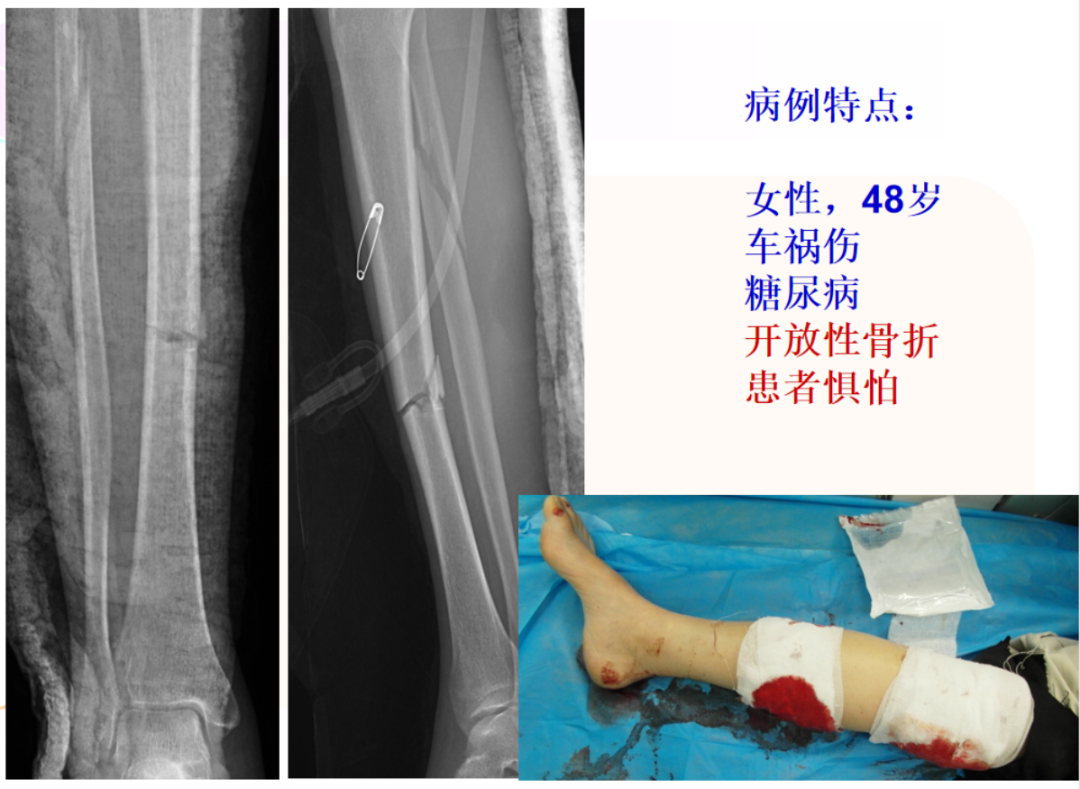

病例特点:男性,32岁,两米高坠落,闭合骨折,分型43A2

治疗:内固定?腓骨固定吗?腓骨先固定吗?下胫腓关节?术后X线片:复位顺序?复位质量?内固定选择?内固定位置?钉数与布局?预后?